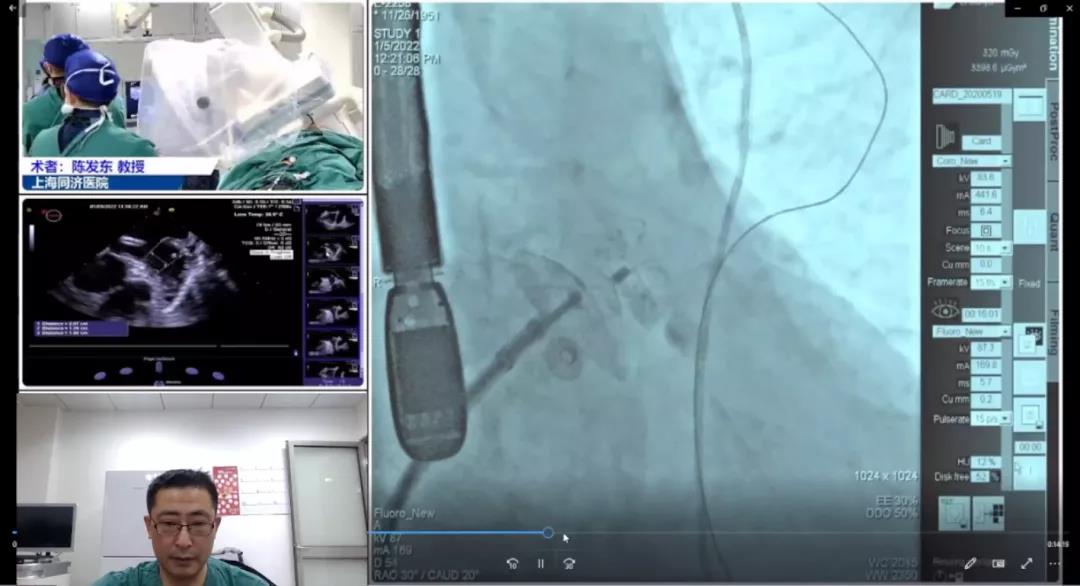

Case 1

上海市同济医院陈发东教授团队

患者男性,70岁,患有持续性房颤、心尖肥厚性心肌病及高血压,拟行房颤消融+左心耳封堵“一站式”手术;颊哂谌樽刺滦杏夜删猜黾胺烤嗬氪┐,成立右心房至左心房通路,在猪尾;は滦行亩煊,丈量左心耳锚定区约为15mm,封堵区约为23mm,结合造影和丈量了局综合思考,选用LAmbre?2032封堵器进行封堵,多角度造影及TEE显示封堵成效梦想,无残存分流,牵拉测试极度不变,切合COST准则,手术获得圆满成功。